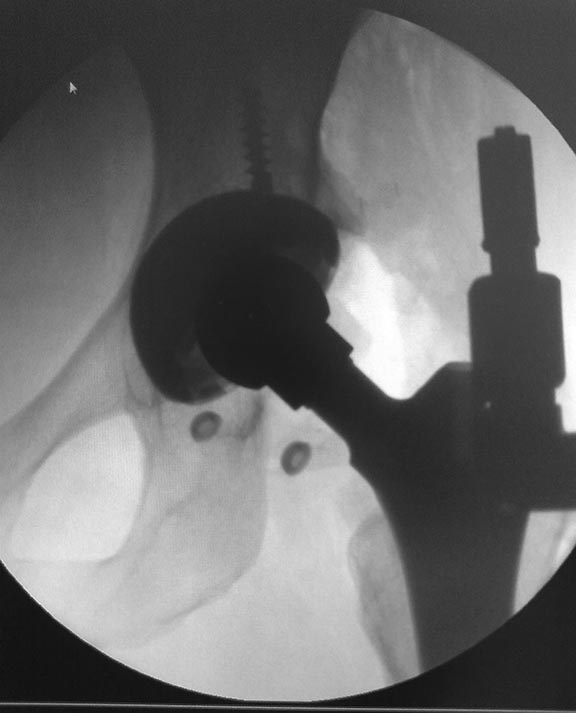

Все получилось из переднего доступа по Лайт-Кегги под эопом конечно

смотрели казалось  нестабильна,но на самом деле чашка не

качалась,остеоинтеграция  была только в зоне винтов , остальное рубцова

ткань -гладкая и блестящая.После сбивания головки бедро в положении

внутренней ротаци сместили вверх и впадина очень хорошо

доступна.Установили чашку DePuy Pinnacle  с антеверсиtq 20 гр.

Востановить офсет удалось с головкой  DePuy +12.Рентген контроль на

С-дуге интрооперационно.